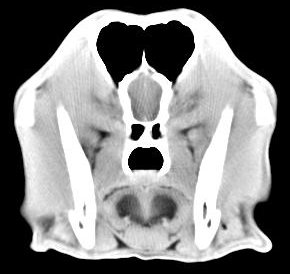

imágenes de TC en el perro | ||||||||||

ejemplo de imágenes de TC en el perro. Nótese la celulitis en la región parotídea izquierda | ||||||||||